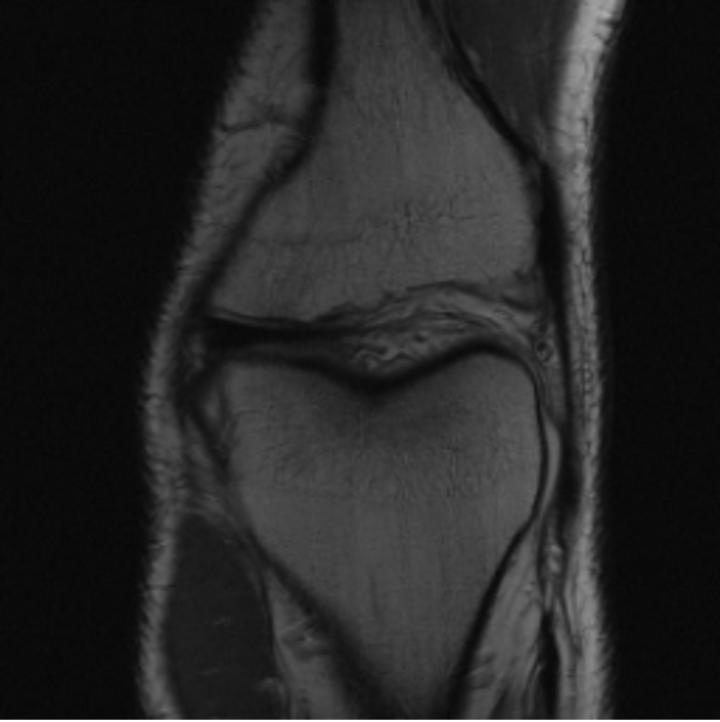

One way to test the generalization capability of the trained X-Diffusion is to test it on a completely different domain from an MRI dataset not seen during training. We report the single-slice results on the test set of knees from NYU fastMRI [33, 80], using the X-Diffusion trained on the BRATS brain MRIs. The test PSNR result is 34.17 and an example is shown in Figure 8. It shows how successfully X-Diffusion can generate knee MRIs (out-of-domain) despite being trained on brains.

Small Knee MRIs clinical study. To qualitatively assess how realistic our generated knee out-of-domain 3D volumes were (produced from a single slice), we gave 20 generated examples alongside their real MRI counterparts to an expert orthopedic surgeon J. F.. He was then asked to identify the real example from a set of 20 MRI pairs. The surgeon correctly identified the real MRI in only 10 out of 20 pairs, could not decide in 3 pairs, and misidentified the generated MRI as real in the remaining 7 pairs. This further validates the generated out-of-domain MRIs.